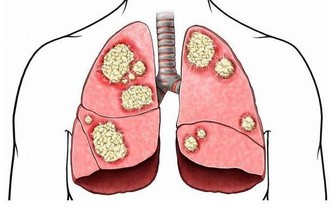

烹調時,多用植物油,可多吃一些魚,海魚含有不飽和脂肪酸,可降低血漿膽固醇,還含有較多的亞油酸,可增加微血管的彈性,預防血管破裂,防止高血壓並發症。